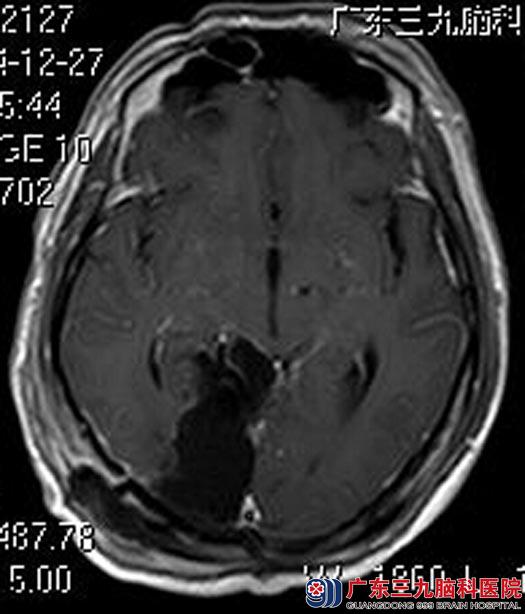

进一步头颅MR检查提示:右侧颞枕部内侧(小脑天幕上、下)示一团块状占位性病变,大小约4.29cm×4.18cm×4.51cm;头颅CTA检查提示:右侧颞枕部内侧(小脑天幕上、下)占位性病变,血供丰富、内示多发细小血管影,双侧大脑后动脉分支包绕病变(右侧为主),考虑脑膜瘤。由于肿瘤血供丰富,经讨论,术前行肿瘤部分供血血管栓塞术,术中栓塞左侧大脑后动脉远端、左侧大脑上动脉分支远端。次日,由鲁明主任主刀在全麻下行经popen入路松果体脑膜瘤切除术,术中见灰白色肿瘤组织,跨小脑幕,血供丰富,边界清晰,予显微镜下逐步分离分块切除,右侧大脑后动脉P3段、右侧小脑上动脉分支主要参与肿瘤供血,予动脉瘤夹肿瘤基底部位于小脑幕,肿瘤镜下全切。术后林先生恢复很好。病理结果:皮细胞型脑膜瘤(WHO I级)。

手术后